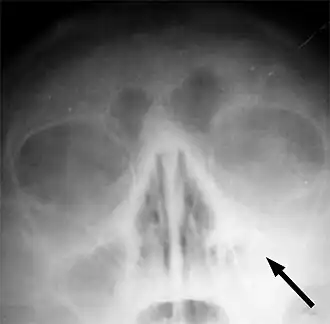

Рентгеновский снимок пазух больного гайморитом (стрелкой обозначено затемнение в области верхнечелюстной пазухи, указывающее на присутствие в ней жидкости) | |

Одним из основных симптомов гайморита является тянущая боль, которая возникает при наклоне туловища вперёд. Подтверждение диагноза производится на основании рентгеновского снимка.

Диагностика синуситов